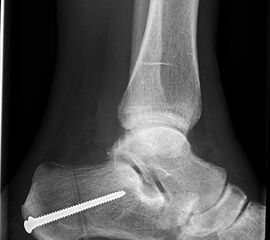

Die stehende OSG ap -Aufnahme kann zunächst das fibulocalcaneare Impingement und im Endstadium laterale OSG Arthrose oder Valgus-Tilt des Talus zeigen.

OSG ap stehend

fibulocalcaneares Impingement

laterale OSG Arthrose, Talus Valgus-tilt